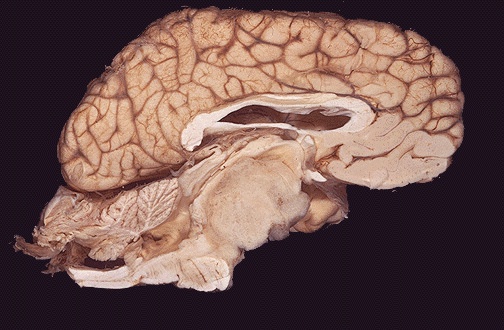

This sagittal section of brain demonstrates a large brainstem glioma. Most gliomas are astrocytomas. [Image contributed by Jeannette J. Townsend, MD, University of Utah]